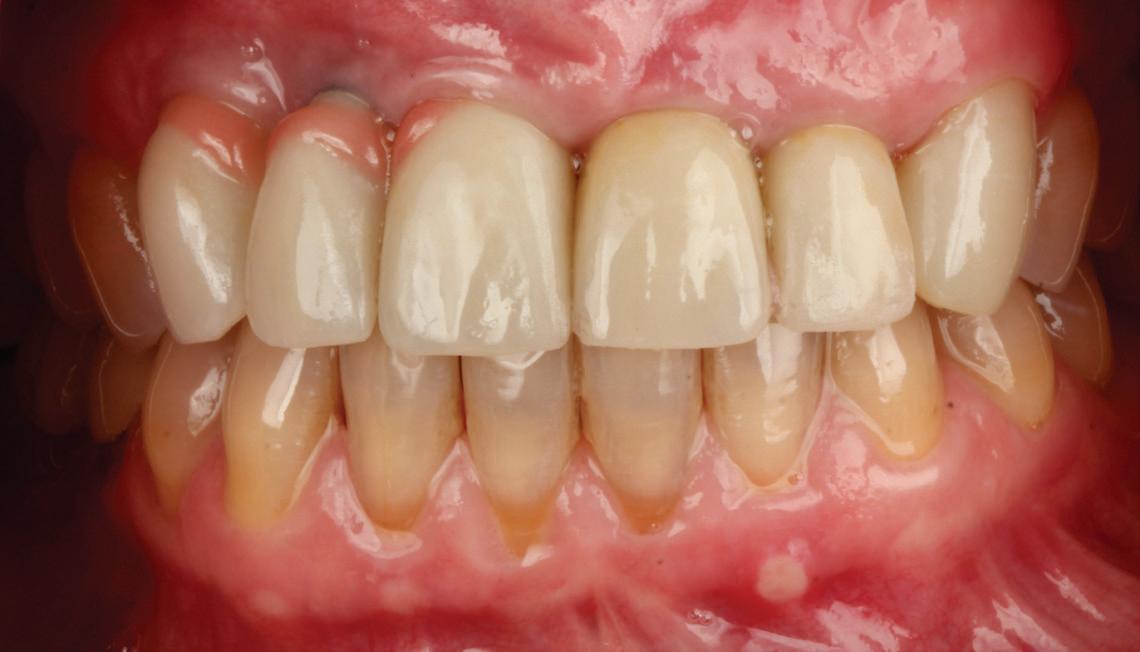

• Pacient cu restaurări deficitare pe dinți compromiși structural, tratamente endodontice eșuate, mobilitate avansată, pungi parodontale profunde, incisiv lateral absent congenital restaurat prin substituție canină inestetică, linie înaltă a zâmbetului. Rezolvarea? Colaborarea cu endodont, parodontolog, ortodont, protetician. Rezultatul? Succes clinic și satisfacția pacientului.

• Chirurgia implantară cu cea mai inteligentă planificare și mai precisă execuție va necesita în continuare un finisaj protetic care funcționează biomecanic și realizează o estetică naturală ideală individuală. Dacă există un aspect al tratamentului protetic cu provocări în era digitală, acesta ar consta în munca artistică minuțioasă a ceramistului, cu modelarea și pictarea dinților pentru a imita natura.

Colaborarea profesională și planificarea ghidată protetic sunt esențiale pentru rezultate predictibile de succes.